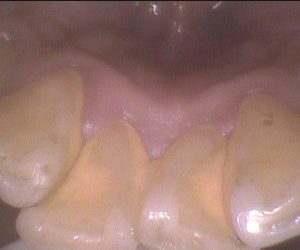

今日のクリーニングです🦷 下の前歯の表側、裏側のクリーニング前後のお写真です📸 歯と歯の間や、歯ぐきのきわに歯石が多く付着していました。 歯ぐきも少し腫れていた […]